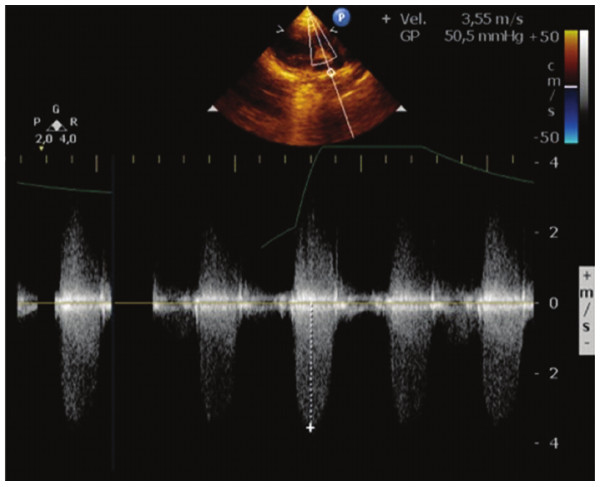

Un niño de 6 años de 15 kg fue derivado a nuestro hospital, debido a disnea. Al examen físico presentaba saturación del 92% aire ambiente, soplo sistólico 4/6 en el área pulmonar y componente pulmonar del segundo ruido disminuido. La presión arterial era de 90/60 mmHg y la frecuencia cardíaca, de 100 latidos por minuto. El ecocardiograma Doppler color y el cateterismo cardíaco revelaron DVSVD, subtipo Fallot, con estenosis valvular y subvalvular pulmonar moderada (Figura 1). Se realizó una angiotomografía computarizada (ATC) multidetectores (Toshiba Aquilion 64 detectores, Japón) con reconstrucción 3D mediante cortes de 0,5mm de espesor. Fue necesario disminuir la frecuencia cardíaca del paciente con una dosis de 1 mg/kg de propranolol oral 6 h antes del estudio para mejorar la adquisición de imágenes. Se evidenció una arteria subclavia derecha aberrante y una anomalía coronaria de arteria descendente anterior originada en la coronaria derecha, cruzando la vía de salida de ventrículo derecho (Figura 2 A). Las imágenes en formato DICOM (Standard Digital Imaging and Communications in Medicine) fueron enviadas a una work station independiente para la creación del modelo cardíaco 3D, habiendo utilizado para ello programas abiertos o libres para diseños asistido por computadora (CAD), como InVesalius 3.0 (Sao Paulo, Brasil), Blender 2.76 (Amsterdam, Holanda) y Meshmixer (California, EE. UU.). Estos programas permitieron limpiar, analizar y procesar las imágenes inicialmente y posteriormente convertirlas a un archivo STL (standard tessellation language) para la impresión 3D. EL modelo del corazón fue construido usando un método semiautomático donde un caparazón (1,5-2 mm de espesor) fue creado alrededor del pool de sangre, con la consiguiente substracción de esta. Se realizó sustracción de las estructuras óseas y de la anatomía no deseada por métodos tradicionales utilizando CAD software. El modelo del corazón fue impreso con la impresora Kikai Labs Maker T125 (Buenos Aires, Argentina), que utiliza extrusión de fibras de polímero termoplásticas (ABS: acrilonitrilo butadieno estireno) y el método de modelo de depósito por fusión (FDM) (Figura 2 B).

El corazón 3D mostró en forma precisa la posición de la CIV con respecto a las estructuras adyacentes, incluidas las válvulas pulmonar, tricúspide y aorta. La planificación virtual, simulación e impresión 3D del molde del parche fue útil para la confección del parche suturado para el túnel. El ecocardiograma Doppler color posoperatorio evidenció una reparación efectiva sin obstrucción residual en el túnel. Se demostró un gradiente valvular pulmonar de 20 mmHg, sin insuficiencia ni shunt residual. Se extubó al paciente en el día 1 poscirugía, requirió antibióticos por un cuadro de infección de vía aérea y recibió el alta al día 14 posoperatorio. El paciente se encuentra asintomático luego de 16 meses de la cirugía. Un ecocardiograma Doppler color evidenció buena función biventricular, sin gradiente significativo en VSVD (13 mmHg), insuficiencia valvular pulmonar leve, sin obstrucción en el túnel.